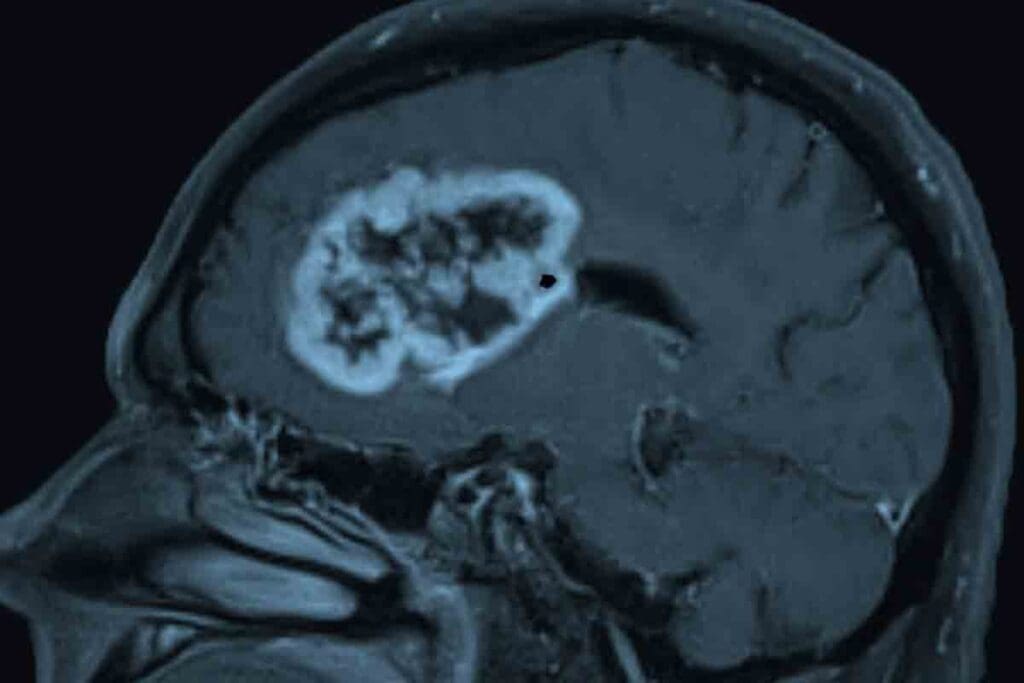

Imaging Studies (MRI, CT Scans)

Imaging is vital for diagnosing pediatric GBM. MRI and CT scans help us see the tumor in the brain. MRI gives us clear images of soft tissues, showing the tumor’s size and where it is.

Common Locations in the Brain

GBM can pop up anywhere in the brain but often shows up in the cerebral hemispheres. It likes the frontal lobe and areas above the tentorium. It can also appear in the brainstem and cerebellum, but that’s less common in kids.

Growth Patterns and Invasiveness

GBMs grow fast and spread into brain tissue. They start in the white matter and can get big before symptoms show. Their ability to spread makes surgery hard, as they can sneak into nearby brain areas.